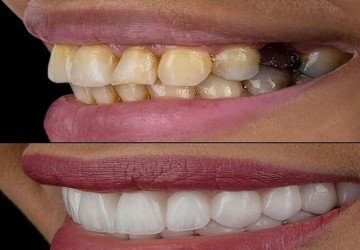

برخی از افراد به هر دلیلی ممکن است دندان های خود را از دست بدهند. همان طور که در عکس بالا...